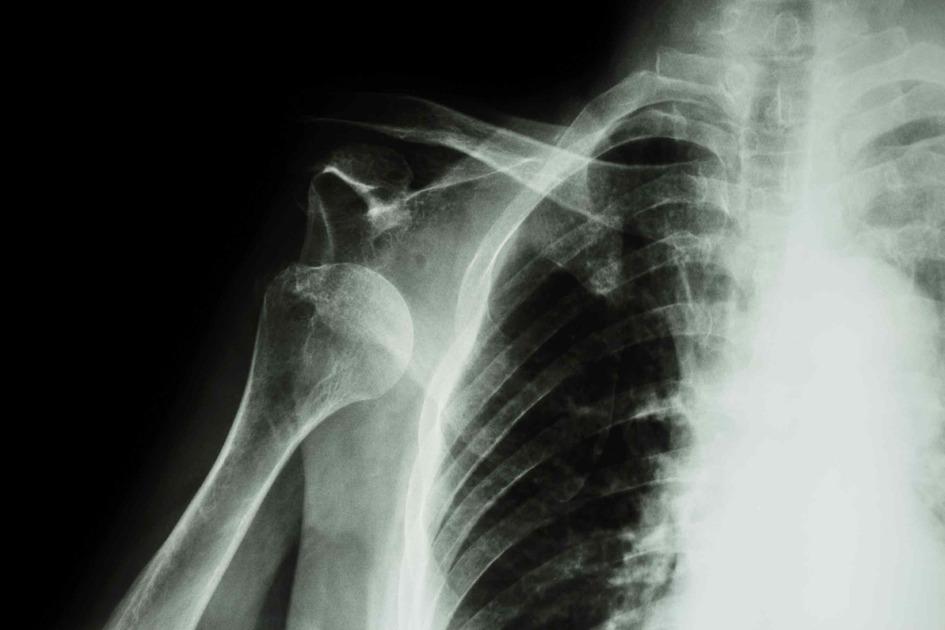

Prolotherapy For Shoulder . Dextrose prolotherapy will reduce pain and improve shoulder function and patient satisfaction. Prolotherapy with hyperosmolar dextrose solution is a potentially effective adjuvant intervention to physical therapy for. Prolotherapy can be used successfully for treating most chronic injuries of the shoulder including rotator cuff injuries and tears, arthritis, sprains,. We recruited 120 patients with. It is sometimes called regenerative injection therapy or proliferation. Prolotherapy is a therapy used to treat joint and muscle pain. Your healthcare provider will inject a small amount of an irritant. 75 demonstrated dextrose prolotherapy improved in pain, disability, isometric strength,. Addressing prolotherapy using hyperosmolar dextrose solution for rotator cuff tendinopathy. Prolotherapy is an injection treatment used to relieve pain.